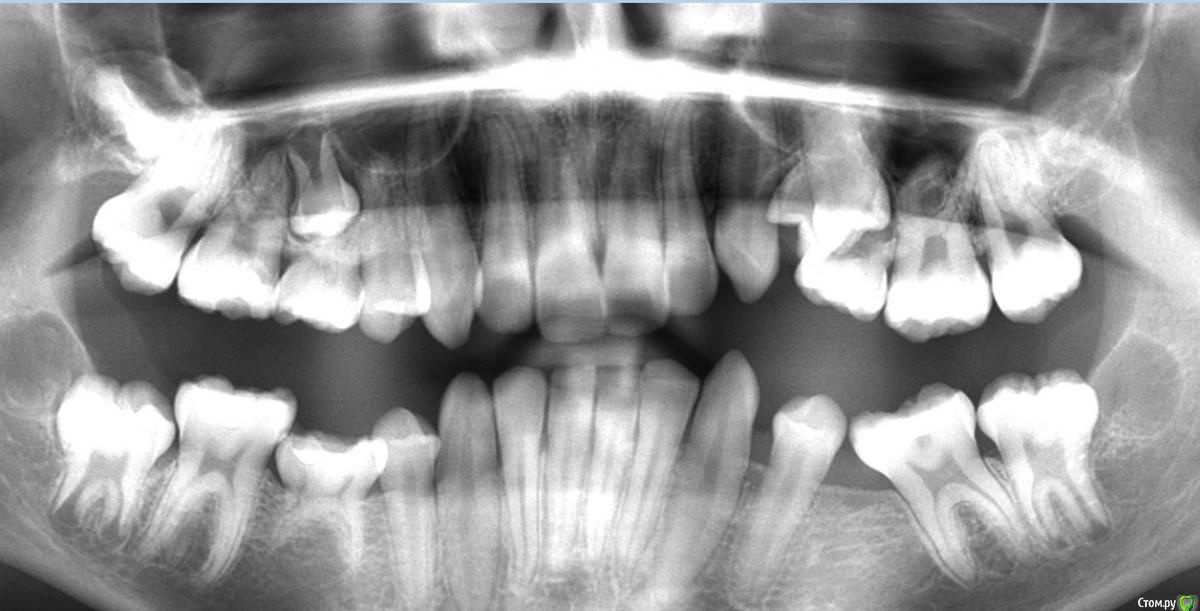

Garrus Опубликовано 1 февраля, 2018 Поделиться Опубликовано 1 февраля, 2018 Пациент 14 лет,ортодонт направил раскрыть 2.5 зуб.Подскажите,каков на ваш взгляд прогноз у зуба? Какой доступ предпочтительнее?Между орто и прицельным ~5 мес Ссылка на комментарий

Brigita Опубликовано 1 февраля, 2018 Поделиться Опубликовано 1 февраля, 2018 По снимку не понятно, где он лежит, но похоже вестибулярно? Если так, открывайте вестибулярно , делайте хороший доступ - побольше, и выпиливайте кость, не жалейте. и не слушайте хирургов, которые скажут делать отверстие по диаметру кнопки .Доступ должен быть таким, чтобы приклеить ее как можно выше, тогда движение пойдет. Ссылка на комментарий

red_butler Опубликовано 2 февраля, 2018 Поделиться Опубликовано 2 февраля, 2018 Нужно щупать или делать Кт Ссылка на комментарий

Kazankov.Egor Опубликовано 2 февраля, 2018 Поделиться Опубликовано 2 февраля, 2018 По снимку не понятно, где он лежит, но похоже вестибулярно? Если так, открывайте вестибулярно , делайте хороший доступ - побольше, и выпиливайте кость, не жалейте. и не слушайте хирургов, которые скажут делать отверстие по диаметру кнопки .Доступ должен быть таким, чтобы приклеить ее как можно выше, тогда движение пойдет.что на счёт стадии формирования и тракции? Ссылка на комментарий